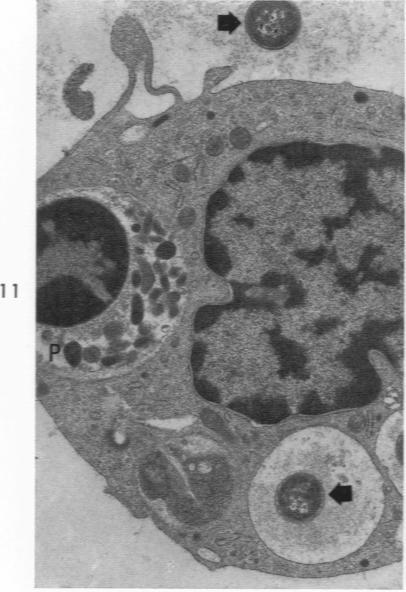

Pneumonic plague in monkeys. An electron microscopic study.

Am J Pathol. 1969 Feb;54(2):167-85.